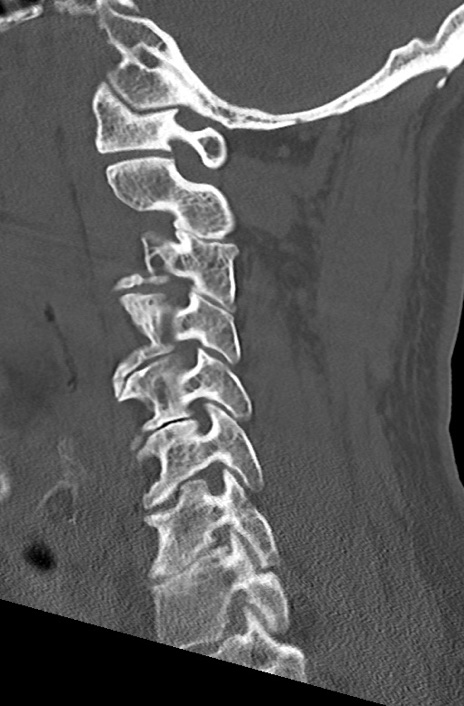

頚椎CT

矢状断像と横断像